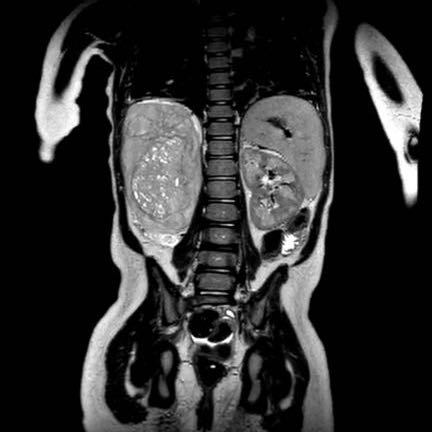

Hình ảnh chuỗi xung T2W mặt phẳng coronal cho thấy một khối u không đồng nhất ở thận trái với các thành phần nang nhỏ.

Khối u ngấm thuốc kém hơn so với phần nhu mô thận bình thường còn lại ở ngoại vi.

Các thành phần đặc của khối u cho thấy hạn chế khuếch tán rõ rệt (mũi tên).

Đây là u Wilms ở bé trai năm tuổi. Hóa trị tiền phẫu được thực hiện theo phác đồ Umbrella của SIOP-RTSG, sau đó tiến hành cắt thận.